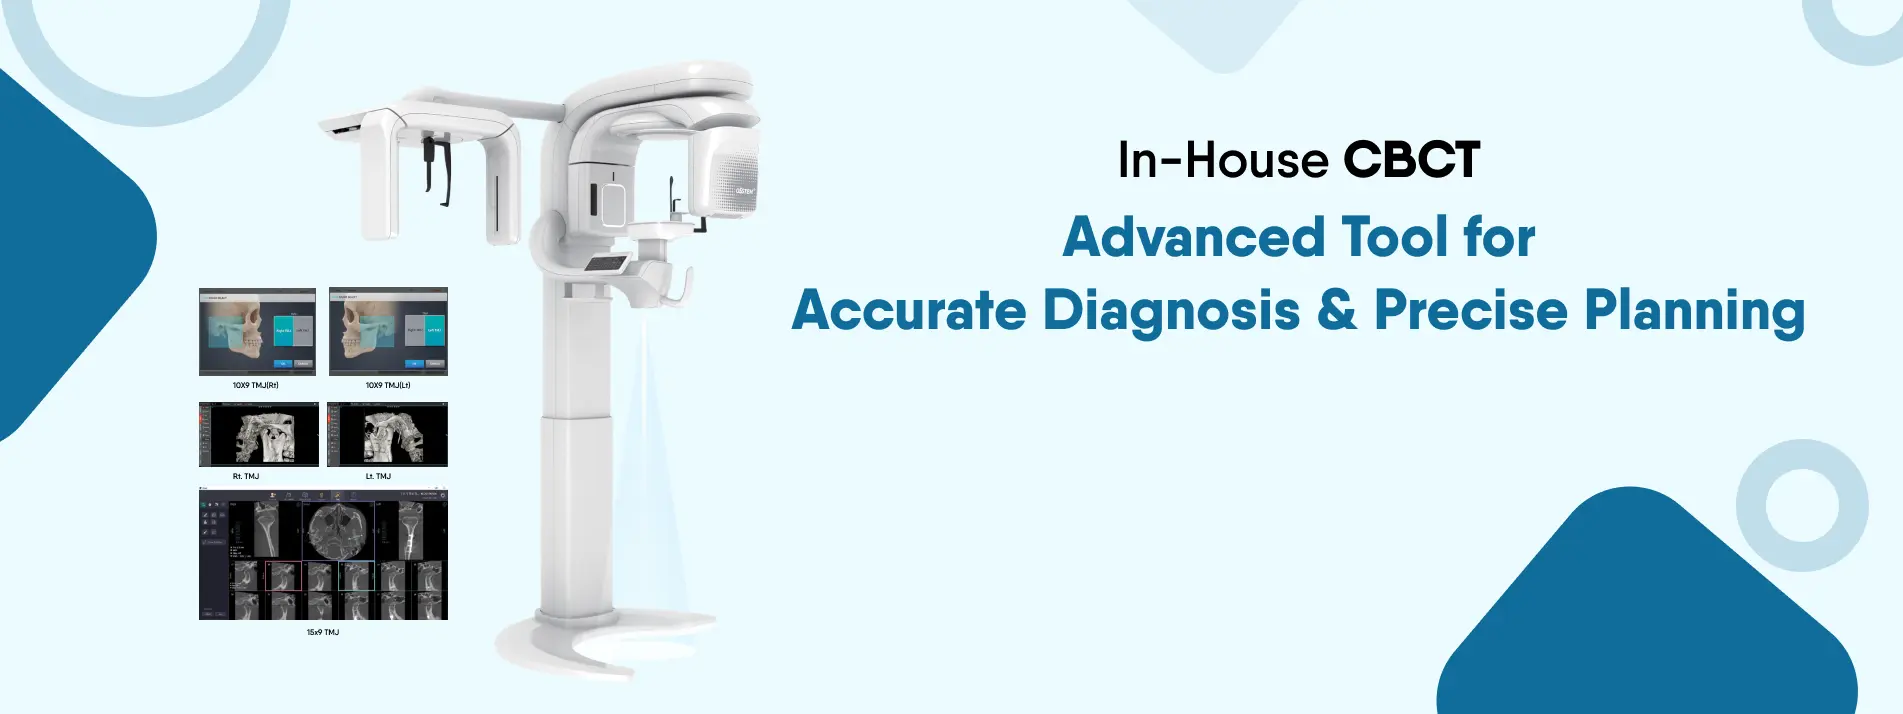

Full Mouth X-RAY

We provide full mouth X-rays for accurate diagnosis, carefully designed for your comfort, delivering fast and precise results.

3D Dental Scan

We offer 3D dental scans, ensuring detailed imaging for advanced treatment, providing fast and accurate results throughout your visit.